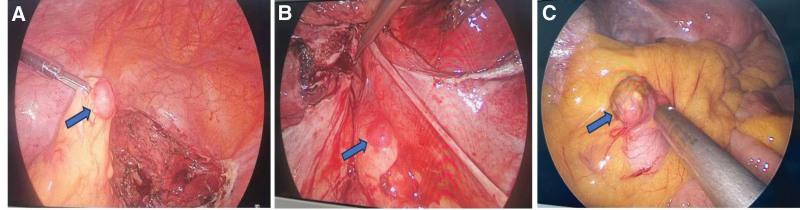

The patient underwent the total hysterectomy, bilateral salpingectomy, pelvic adhesiolysis, omental mass resection, mesenteric mass resection, and pelvic peritoneal mass resection. All specimens were sent for rapid frozen examination and showed to be leiomyomas.

The single-port gasless approach did not achieve the desired reduction in fibroid recurrence, as anticipated by the surgeon. The act of pulling the tumor towards the abdominal incision for resection, on the contrary, may serve as an iatrogenic factor contributing to postoperative recurrence of CL into peritoneal dissemination leiomyomatosis. The single-port gasless assisted bag may be a more suitable option for myomectomy. The utmost effort should be made to prevent the potential recurrence of myoma caused by iatrogenic factors.